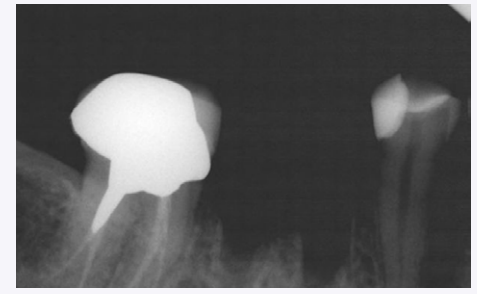

Periapical radiograph after tooth extraction.

Periapical radiograph taken 3 months post-socket augmentation.

A 39-year-old woman presented with a failing mandibular right first molar under a fixed PFM prosthesis. The patient was in good health and had no medical contra-indications that would prevent routine dento-alveolar surgery. Pre-operative photographs and periapical radiographs were taken of the site. After bridge removal, the tooth was deemed hopeless. It was sectioned and extracted in an atraumatic manner using periotomes and luxators (Figs. 1-3).